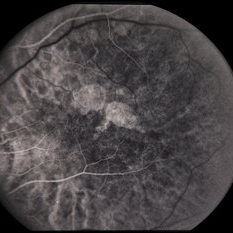

---thumb.jpg/image-square;max$300,300.ImageHandler) Age Related Macular Degeneration - Geographic Atrophy

Age Related Macular Degeneration - Geographic Atrophy

May 3 2013 by Suber S. Huang, MD, MBA, FASRS

Geographic Atrophy.

Imaging device: Retina Diseases Imaging Reading Center

Condition/keywords: advanced geographic atrophy, atrophic scar, atrophic spot, geographic atrophy, macula lesion, pigment epithelial atrophy, red-free, window defect